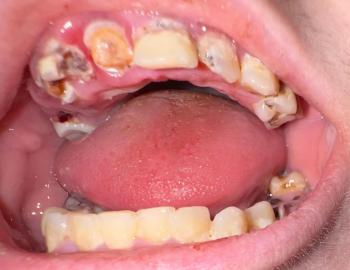

Dental Case Analysis – Full Mouth Panoramic X-Ray With Multiple Infection Sites

This panoramic dental X-ray shows a full-mouth view of the maxilla and mandible. Several teeth demonstrate radiographic signs of infection, bone loss, and previous dental treatment. The findings suggest chronic, multi-site dental pathology rather than a single isolated issue.

Diagnosis

Chronic apical periodontitis affecting multiple teeth

Generalized dental infection with localized bone loss

Long-standing inflammatory dental condition

Panoramic X-rays often reveal hidden, silent infections that are not yet symptomatic. Early intervention and staged treatment planning are critical to preserve remaining bone and teeth. Full-mouth cases require coordinated, long-term care.